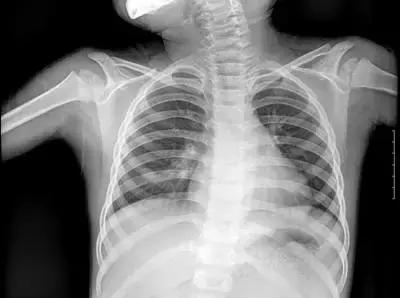

X光:主要看“密度”, 擅长骨折、肺脏病变

但人体各组织结构的密度不同,X线穿透时被吸收的量不同,就形成了黑白灰分明、层次显著的“片子”。看图举例子:

▲X射线成像图

骨骼、钙化灶、体内液体等(听起来质地较厚重的组织),吸收X光较多,因此形成白色影像,也就是传说中的“高密度影”,上图的上臂、肋骨就是如此。

呼吸道、胃肠道、脂肪组织(听起来质地较疏松),吸收X光较少,在片子上呈现黑色影像,即“低密度影”,图中含气体较多的肺脏是代表。

再就是密度居中的实质器官、 肌肉、结缔组织,比如心脏,在片子上呈现的影像介于黑白两色之间。

X光片“泾渭分明”的特点帮医生辨别身体的不同病变。

骨折、肋骨病变,密度高的骨骼白色影像哪里出问题一目了然,比如液气胸等肺部及气道病变,肺脏的黑色影像中就会混入明亮的白色。